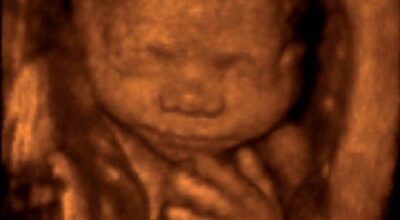

La evolución del feto a través de ecografías

Ecografía de 15 semanas: feto de frente presentado en ecografía 3D.